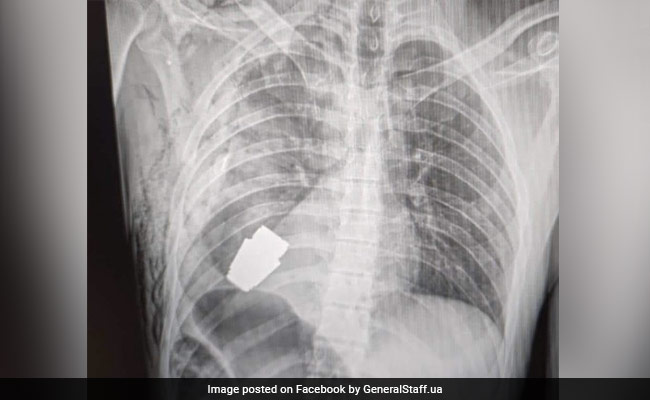

Ukraine Army Chief's Close Aide Dies After Grenade Hidden In Birthday Gift Explodes

- World News | Edited by Ritu Singh

Ukraine Military Adviser Received Grenade As Gift, Dies After It Explodes

A close adviser to the commander-in-chief of the Ukrainian army was killed when a grenade among his birthday gifts exploded on Monday, officials said.